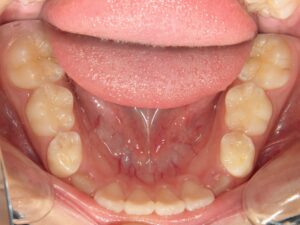

第1期治療終了時

口腔内写真

治療結果

上の前歯のデコボコが改善

上の歯の狭さが改善

目標の永久歯萌出スペースを確保

第2期治療へ移行

上の前歯の裏側に保定装置(Fixリテーナー)を装着し、全ての永久歯萌出後に全顎矯正を行い、全体的な咬み合わせの調整を行います。